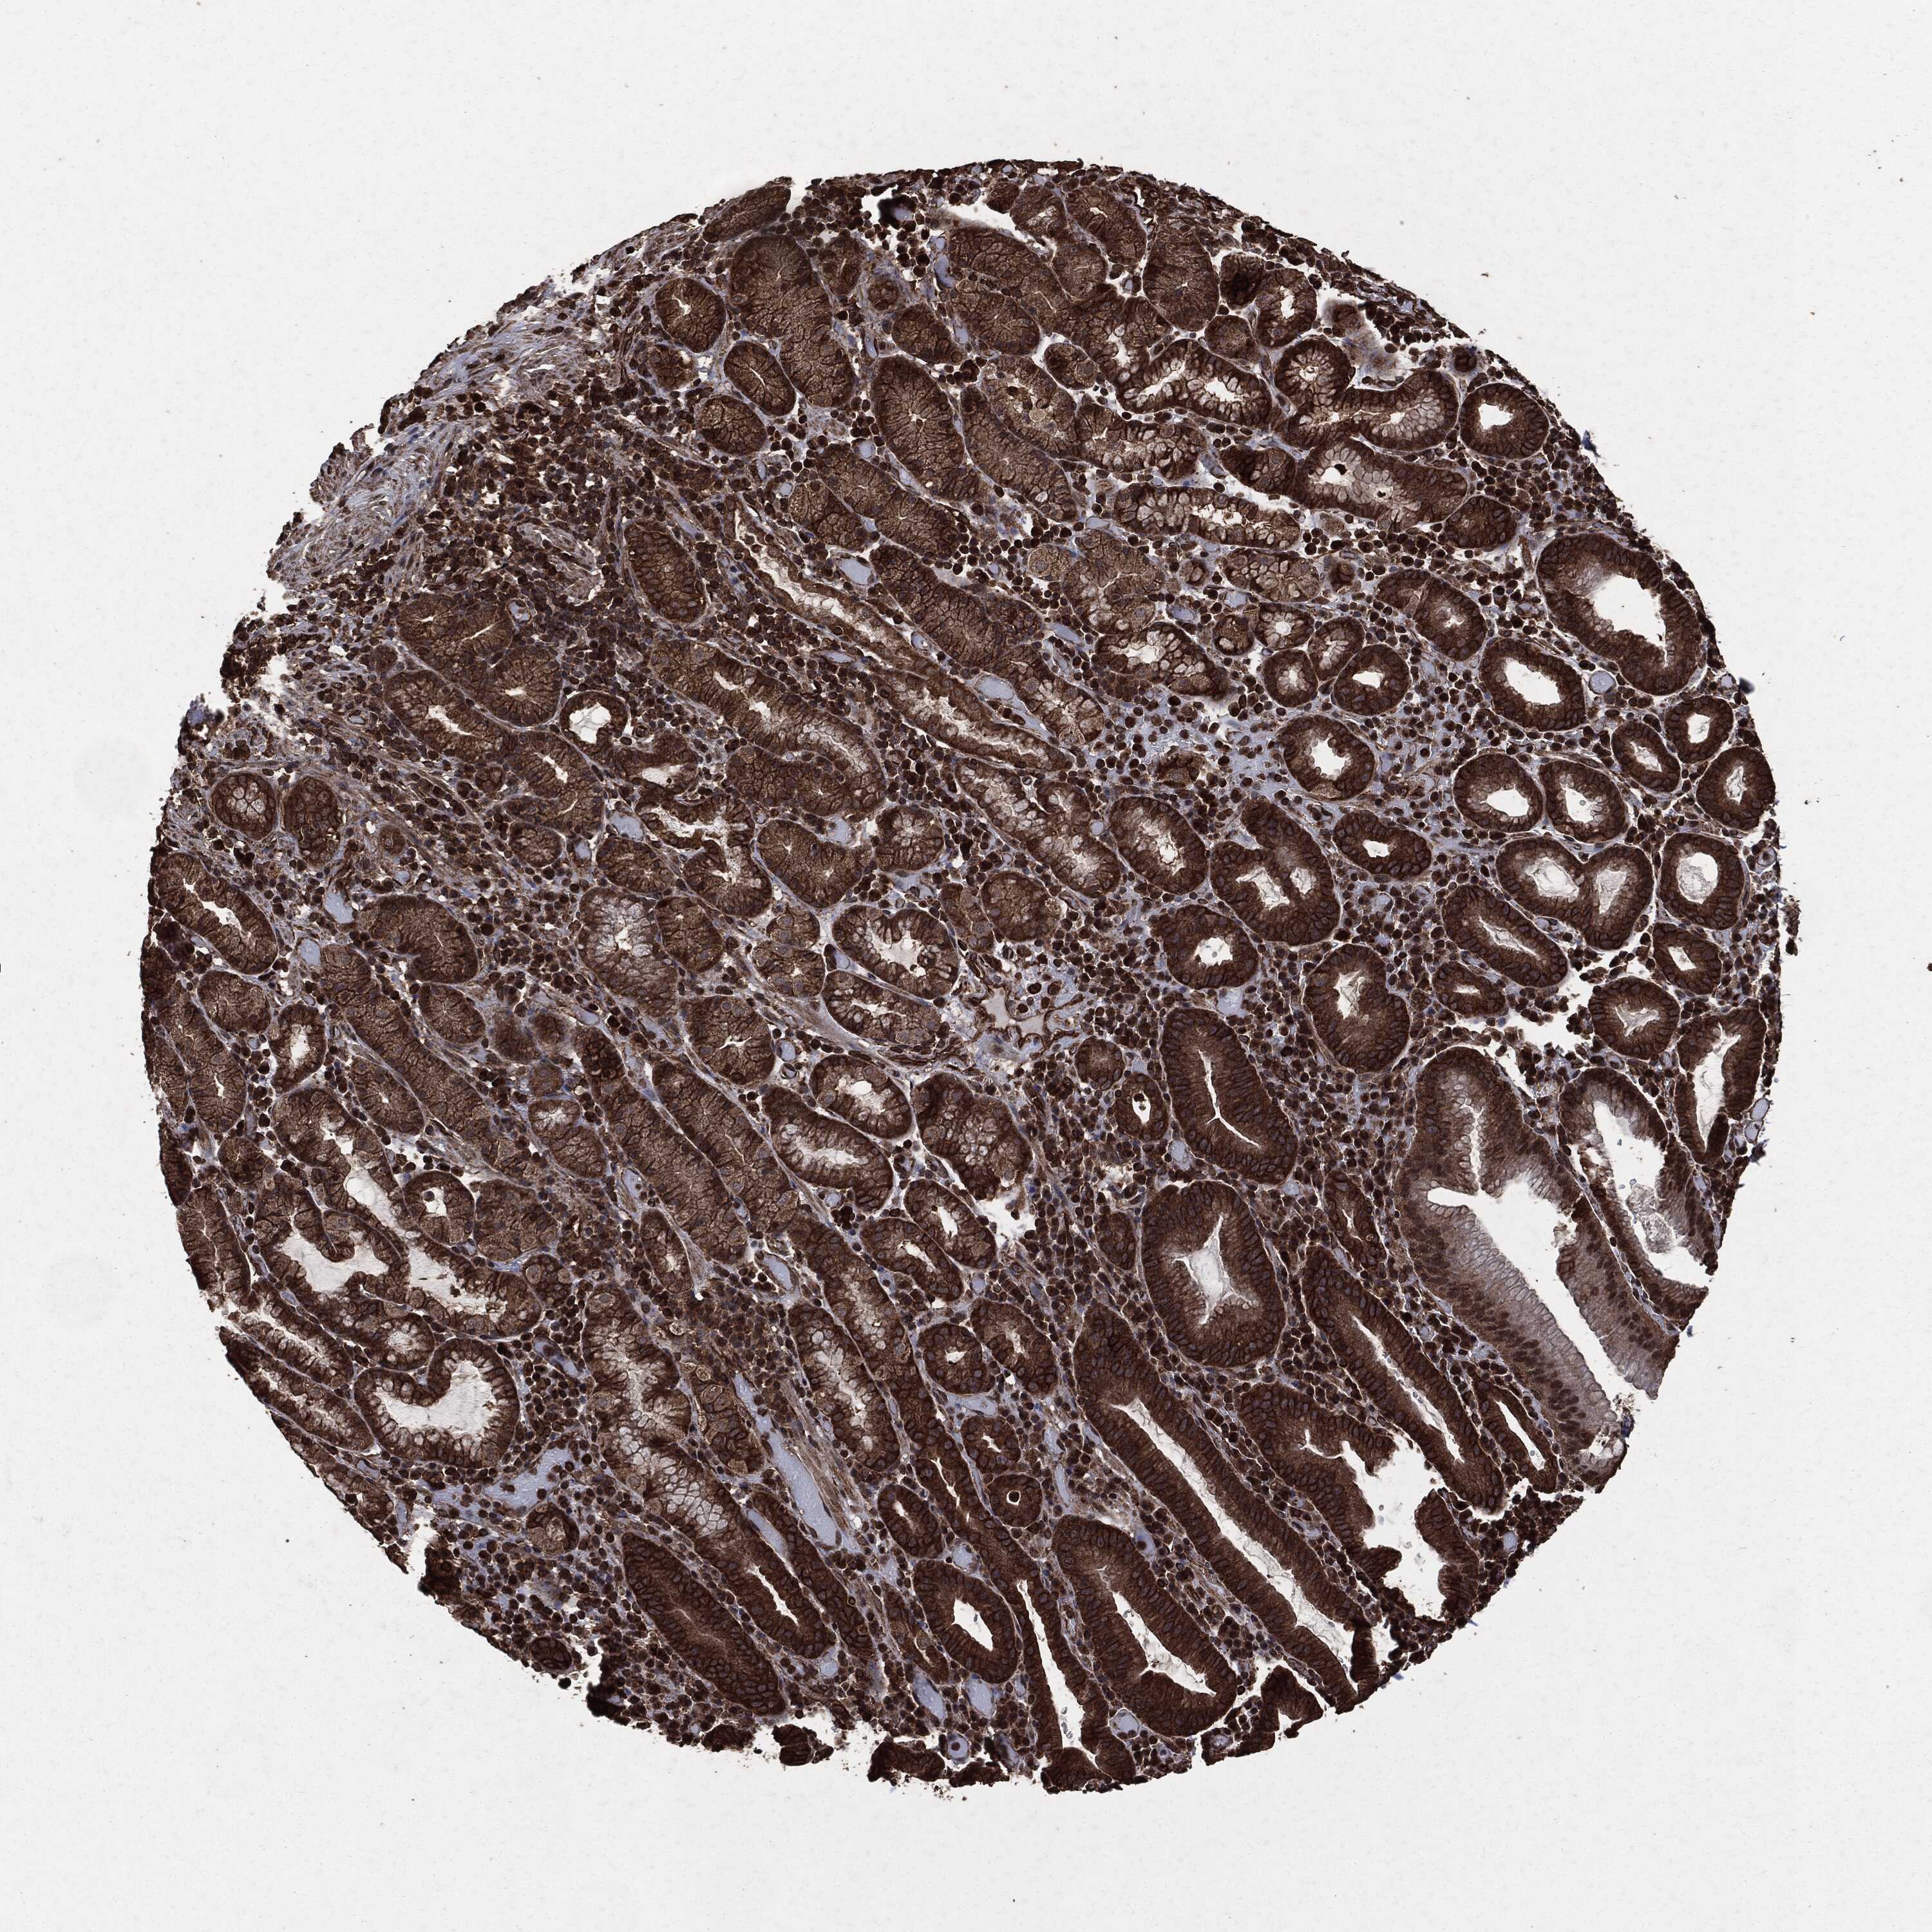

STOMACH CANCER - Protein expressioni

A mouse-over function shows sample information and annotation data. Click on an image to view it in a full screen mode. Samples can be filtered based on level of antibody staining by selecting one or several of the following categories: high, medium, low and not detected. The assay and annotation is described here.

Note that samples used for immunohistochemistry by the Human Protein Atlas do not correspond to samples in the TCGA dataset.

Antibody stainingi

Antibody staining in the annotated cell types in the current human tissue is reported as not detected, low, medium, or high, based on conventional immunohistochemistry profiling in selected tissues. This score is based on the combination of the staining intensity and fraction of stained cells.

Each image is clickable and will lead to virtual microscopy that enables deeper exploration of all samples and also displays staining intensity scores, fraction scores and subcellular localization as well as patient and tissue information for each sample.

HPA049830

CAB002015

CAB080330

CAB080331

CAB080332

Staining

High

Medium

Low

Not detected

Intensity

Strong

Moderate

Weak

Negative

Quantity

>75%

75%-25%

<25%

None

Location

Nuclear

Cytoplasmic/membranous

Cytoplasmic/membranous,nuclear

Adenocarcinoma, NOS

Adenocarcinoma, High grade